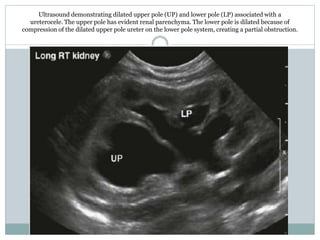

Ultrasound demonstrating dilated upper pole (UP) and lower pole (LP) associated with a

ureterocele. The upper pole has evident renal parenchyma. The lower pole is dilated because of

compression of the dilated upper pole ureter on the lower pole system, creating a partial obstruction.